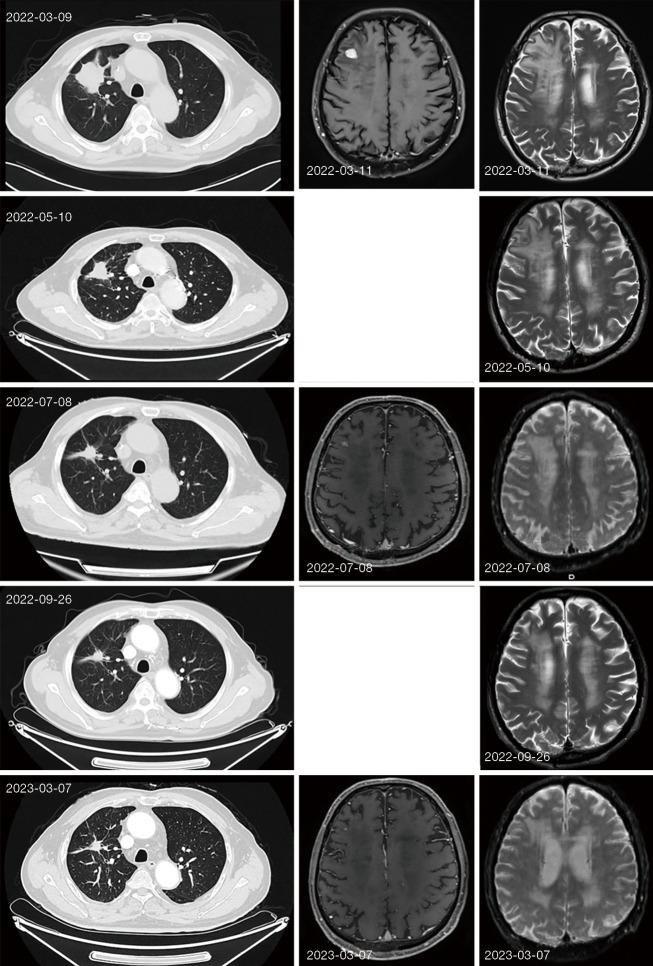

In our study, we report a patient with advanced NSCLC combined with brain metastases, clinical stage IV (c.T3N0M1b), (+) detected by next-generation sequencing (NGS) technology, direct use of sotorasib, an inhibitor of , as first-line therapy. The patient was treated with 4 months of oral therapy, had significant partial remission (PR), and remained in stable disease (SD) for nearly 9 months of follow-up, with no other side effects. Further extension of the follow-up period is needed to assess the impact of sotorasib as first-line therapy on patient survival. A series of clinical trials in phase 3 is ongoing, covering the first-line usage widespread.

在我们的研究中,我们报告了一名晚期 NSCLC 合并脑转移的患者,临床分期为 IV 期(c.T3N0M1b),通过下一代测序(NGS)技术检测到该突变(+),直接使用索托拉西布(一种该抑制剂)作为一线治疗。该患者接受了 4 个月的口服治疗,获得了显著部分缓解(PR),并且在近 9 个月的随访中病情保持稳定(SD),未出现其他副作用。需要进一步延长随访期以评估索托拉西布作为一线治疗对患者生存的影响。一系列 3 期临床试验正在进行中,涵盖广泛的一线用法。